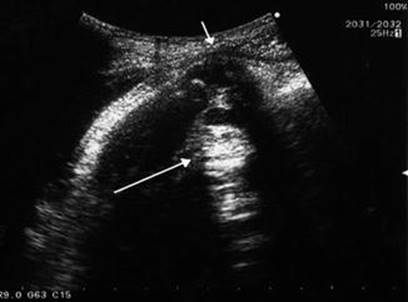

16.7.1 Transvaginal/Transabdominal Ultrasound

A transvaginal and transabdominal ultrasound should be performed to search direct and indirect findings of suspected uterine rupture. Direct signs are thinned wall with bulging of fetal parts (Fig. 16.6) or for visualization of the rupture. The fetus can be partly or completely out of the uterus (Fig. 16.7). Indirect signs are free peritoneal fluid (blood) especially in the pouch of Douglas, extraperitoneal hematoma, intrauterine blood, empty uterus, gestational sac above the uterus (Fig. 16.8), and large uterine mass with gas bubbles [183, 184, 207].

Fig. 16.6

An abdominal ultrasound image of the uterine wall and the fetal minor part. Small arrow indicates a thin uterine wall, which is slightly bulging. Beneath the thin uterine wall, a fetal minor part (large arrow) is visible, which was palpated as a hard mass through the abdomen [184]